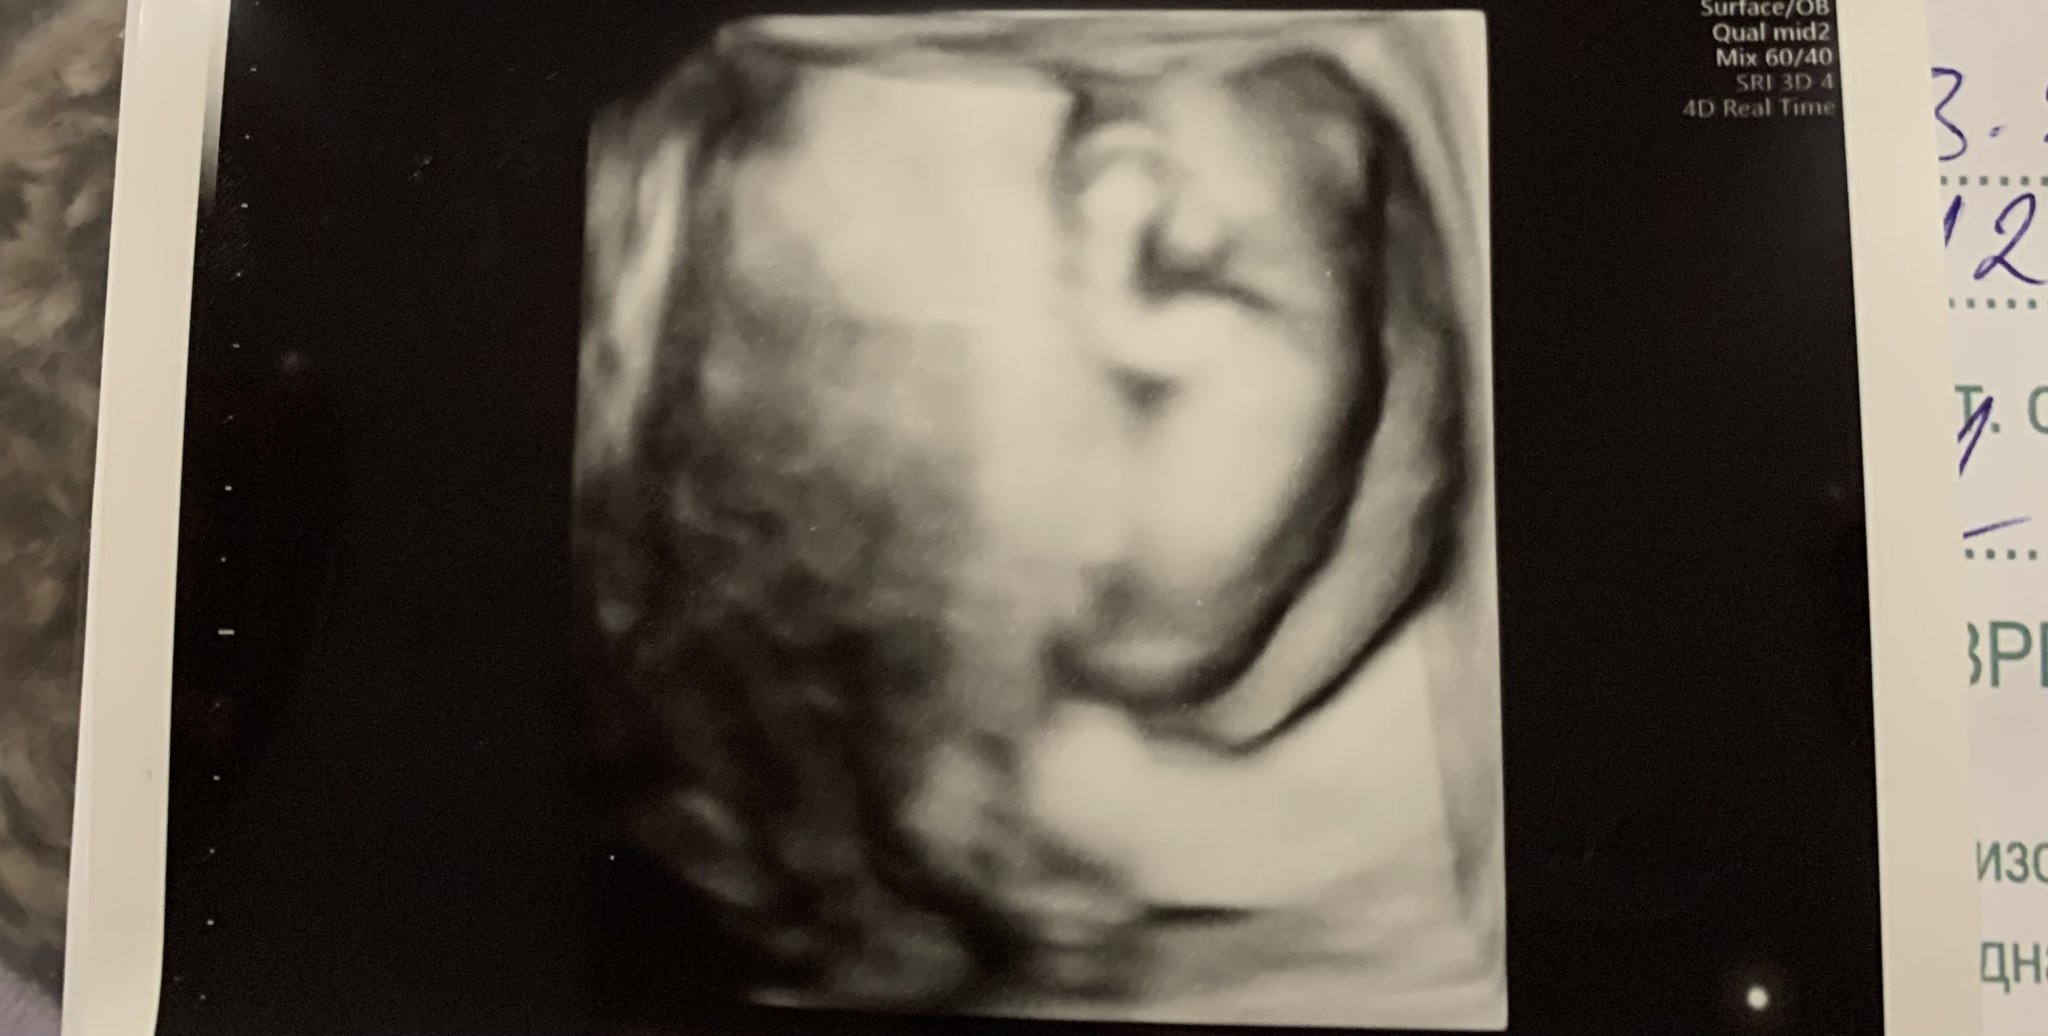

Интересно ми е да попитам и Вас, дали Ви прилича на момиченце или момченце?

Понеже моите близки са единодушни, че прилича на момченце по телосложение, въпреки, че все още е рано, а и си показва само гръбчето за сега 😁

Alisa18, много е сладко и красиво бебчето ти, но според мен е несериозно по телосложение да се определя пола. 😀

Аз пък съм вдивена колко ясно се е очертало бебето на тази снимка.

Така ли вече изглеждат нашите фетуси? На приложението ми на телефона, още на човек не прилича. Аз съм на ехограф другия понеделник, затова се чудя.

Доста добре е оформено на Alisa18 бебочето, да. Бързо растат точиците и наистина е удивително, как за толкова кратък срок вече са си човечета.

Alisa18, не знам какъв пол е бебчето ти, но определено е голям сладур! Да е живо и здраво!

Аз бях на преглед днес, 10 г.с., видяхме как малкото създание, вече 3.48 см, шава с ръчички и ми стана много мило. Но наистина от доста по-далечен изглед е снимката, която ми дадоха днес. Предполагам, че зависи от капацитета на ехографите или пък докторите не се сещат да zoom-нат?

Мисля, че на Алиса е показано на 4D опцията на ехографа, затова е така. Simple Smile

Ехографската снимка, която прикачих е направена миналата седмица, когато вече бебчето беше 12 г.с и е на 4D, тогава ми направиха и феталната морфология + биохимичен скрининг.

Аз преди това съм ходила на преглед последно в 6 г.с и видях само едно продълговато ембрионче 😁